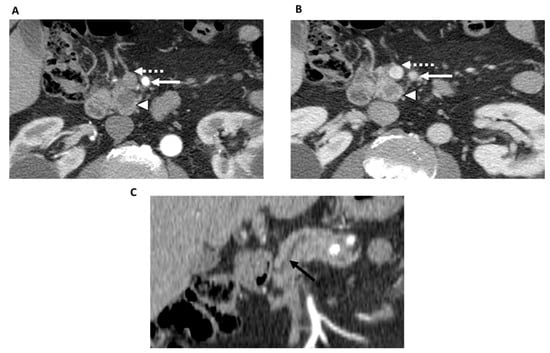

- Jang, J.K.; Byun, J.H.; Kang, J.H.; Son, J.H.; Kim, J.H.; Lee, S.S.; Kim, H.J.; Yoo, C.; Kim, K.P.; Hong, S.M.; et al. CT-determined resectability of borderline resectable and unresectable pancreatic adenocarcinoma following FOLFIRINOX therapy. Eur. Radiol. 2021, 31, 813–823. [Google Scholar] [CrossRef]

| Jang et al. [40], 2021 (South Korea) | 64 | -NCCN resectability criteria including extent of soft tissue contacting arteries and veins, depth of soft tissue contacting arteries and veins, contrast enhancement of the tumor, and of soft tissue surrounding arteries and veins, and tumor size. | -Chemo | 2 GI radiologists | -Only low contrast enhancement of the soft tissue contacting the artery (£ 46.4 HU) was significantly associated with R0 resection (adjusted odds ratio = 7.4; p = 0.01). |